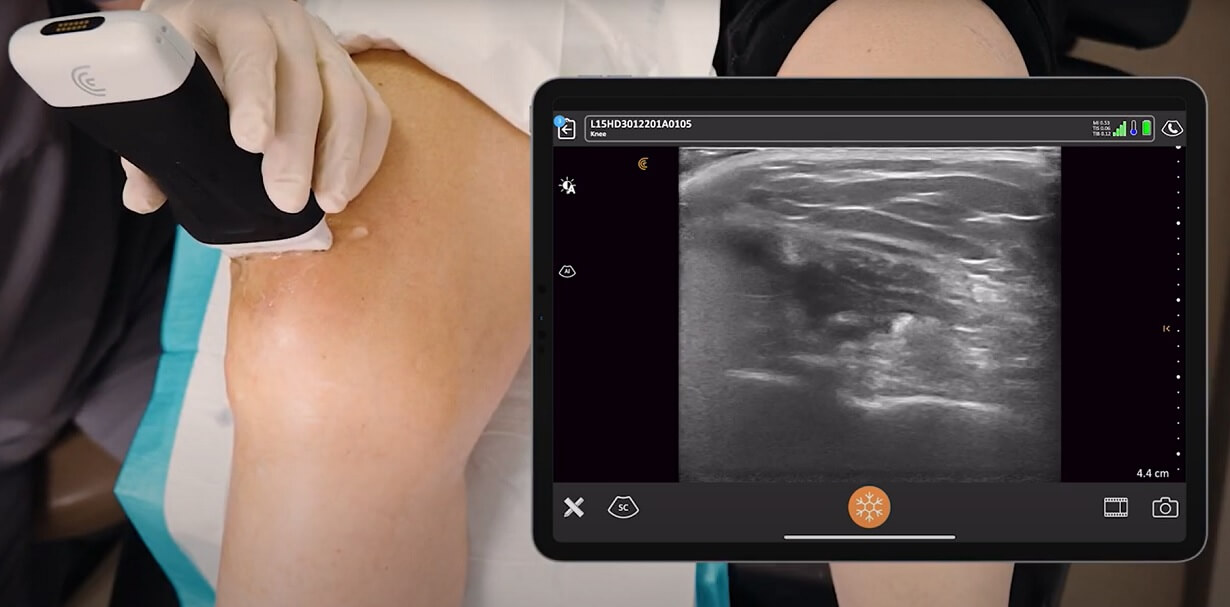

Ovaj pregled se izvodi pomoću posebnog uređaja koji se naziva transduktor (ultrazvučna sonda), koji šalje ultrazvučne talase unutar mekih tkiva kolena.

Ovi talasi se odbijaju (ultrazvučni “eho”) od različitih struktura – kao što su mišići, tetive, ligamenti i tečnosti – i zatim se pretvaraju u slike na ekranu računara u realnom vremenu.

Noga će biti postavljena tako da radiolog ili sonograf može lako da pristupi kolenu. Zatim će lekar naneti jedan poseban prozirni gel na bazi vode na koleno.

Ovaj gel pomaže da ultrazvučna sonda, odnosno transduktor ostvari bolji kontakt sa kožom, obezbeđujući precizan prenos ultrazvučnih talasa.

Nakon toga, lekar će laganim pokretima i uz blagi pritisak pomerati transduktor preko različitih površinskih delova kolena – napred, sa strane i pozadi.

Istovremeno, lekar gleda i prati na ekranu računara unutrašnje strukture kolena u realnom vremenu.

Ove slike se formirau na osnovu ultrazvučnih talasa koji se šalju u unutrašnje strukture kolena. Zatim, ovi talasi se odbijaju od tih struktura, što se na monitoru računara prikazuje kao slika.

Lekar može zamoliti pacijenta da savije ili ispravi koleno kako bi bolje procenio na koji način se tetive i ligament ponašaju, kao i da li je koleno stabilno.

Ponekad lekar može koristiti kolor dopler za procenu protoka krvi, što pomaže u otkrivanju upale ili povećane vaskularnosti u povređenim područjima.